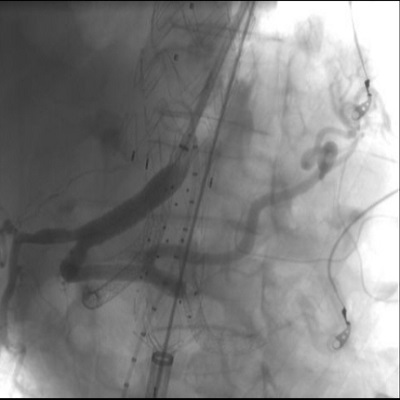

L’intervento endovascolare ha previsto il posizionamento di una serie di endoprotesi: una per l’aorta toracica, una ramificata per i vasi viscerali e una terza endoprotesi aorto-bisiliaca.

L’aneurisma dell’aorta toraco-addominale è una condizione rara ma grave, che richiede interventi altamente specialistici per preservare l’aorta e i rami viscerali. Le tecniche endovascolari avanzate permettono di affrontare patologie complesse come questa, evitando i rischi e la lunga degenza legati alla chirurgia tradizionale, che comporta elevata mortalità e lunghi tempi di terapia intensiva.